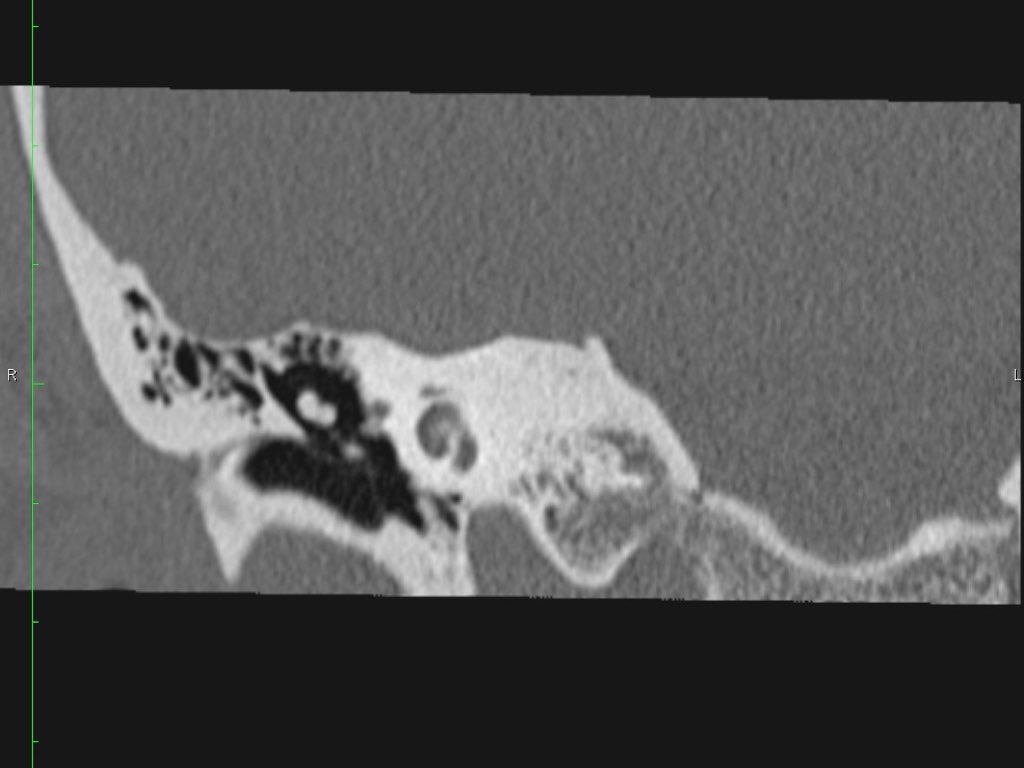

Màng nhĩ

Màng nhĩ hay còn gọi là màng tai, là một màng hình nón ngăn cách tai ngoài với tai giữa.

Pars flaccida là phần trên mỏng manh của màng nhĩ, liên quan đến rối loạn chức năng vòi nhĩ và cholesteatoma.

Pars tensa có kích thước lớn hơn và chắc hơn, thường liên quan đến các trường hợp thủng màng nhĩ.

Cán búa (manubrium) của xương búa được gắn vào phần trung tâm của màng nhĩ, vùng này được gọi là rốn nhĩ (umbo).